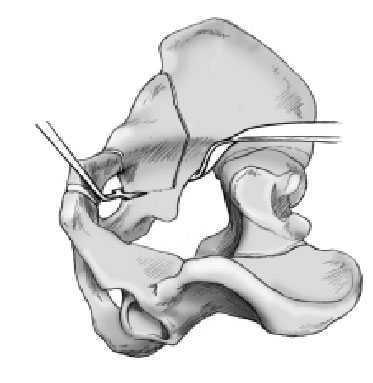

Figura 10 La primera de las tres osteotomías consiste en la sección de la rama iliopubiana. Mediante la flexión a 45º de la cadera, se expone fácilmente la rama ilioinguinal entre el músculo

psoas con el nervio femoral lateral y el paquete vasculonervioso medial. Se protegen las partes blandas y el nervio obturador, que yacen inmediatamente por debajo del hueso con un separador de Hohmann. Se debería comprobar con escopia que la osteotomía no está demasiado cercana al acetábulo. Debería hallarse al menos 1 cm medialmente respecto a la eminencia iliopectínea. La osteotomía se realizará con un motor con sierra oscilante; Los fragmentos se movilizarán con el escoplo.